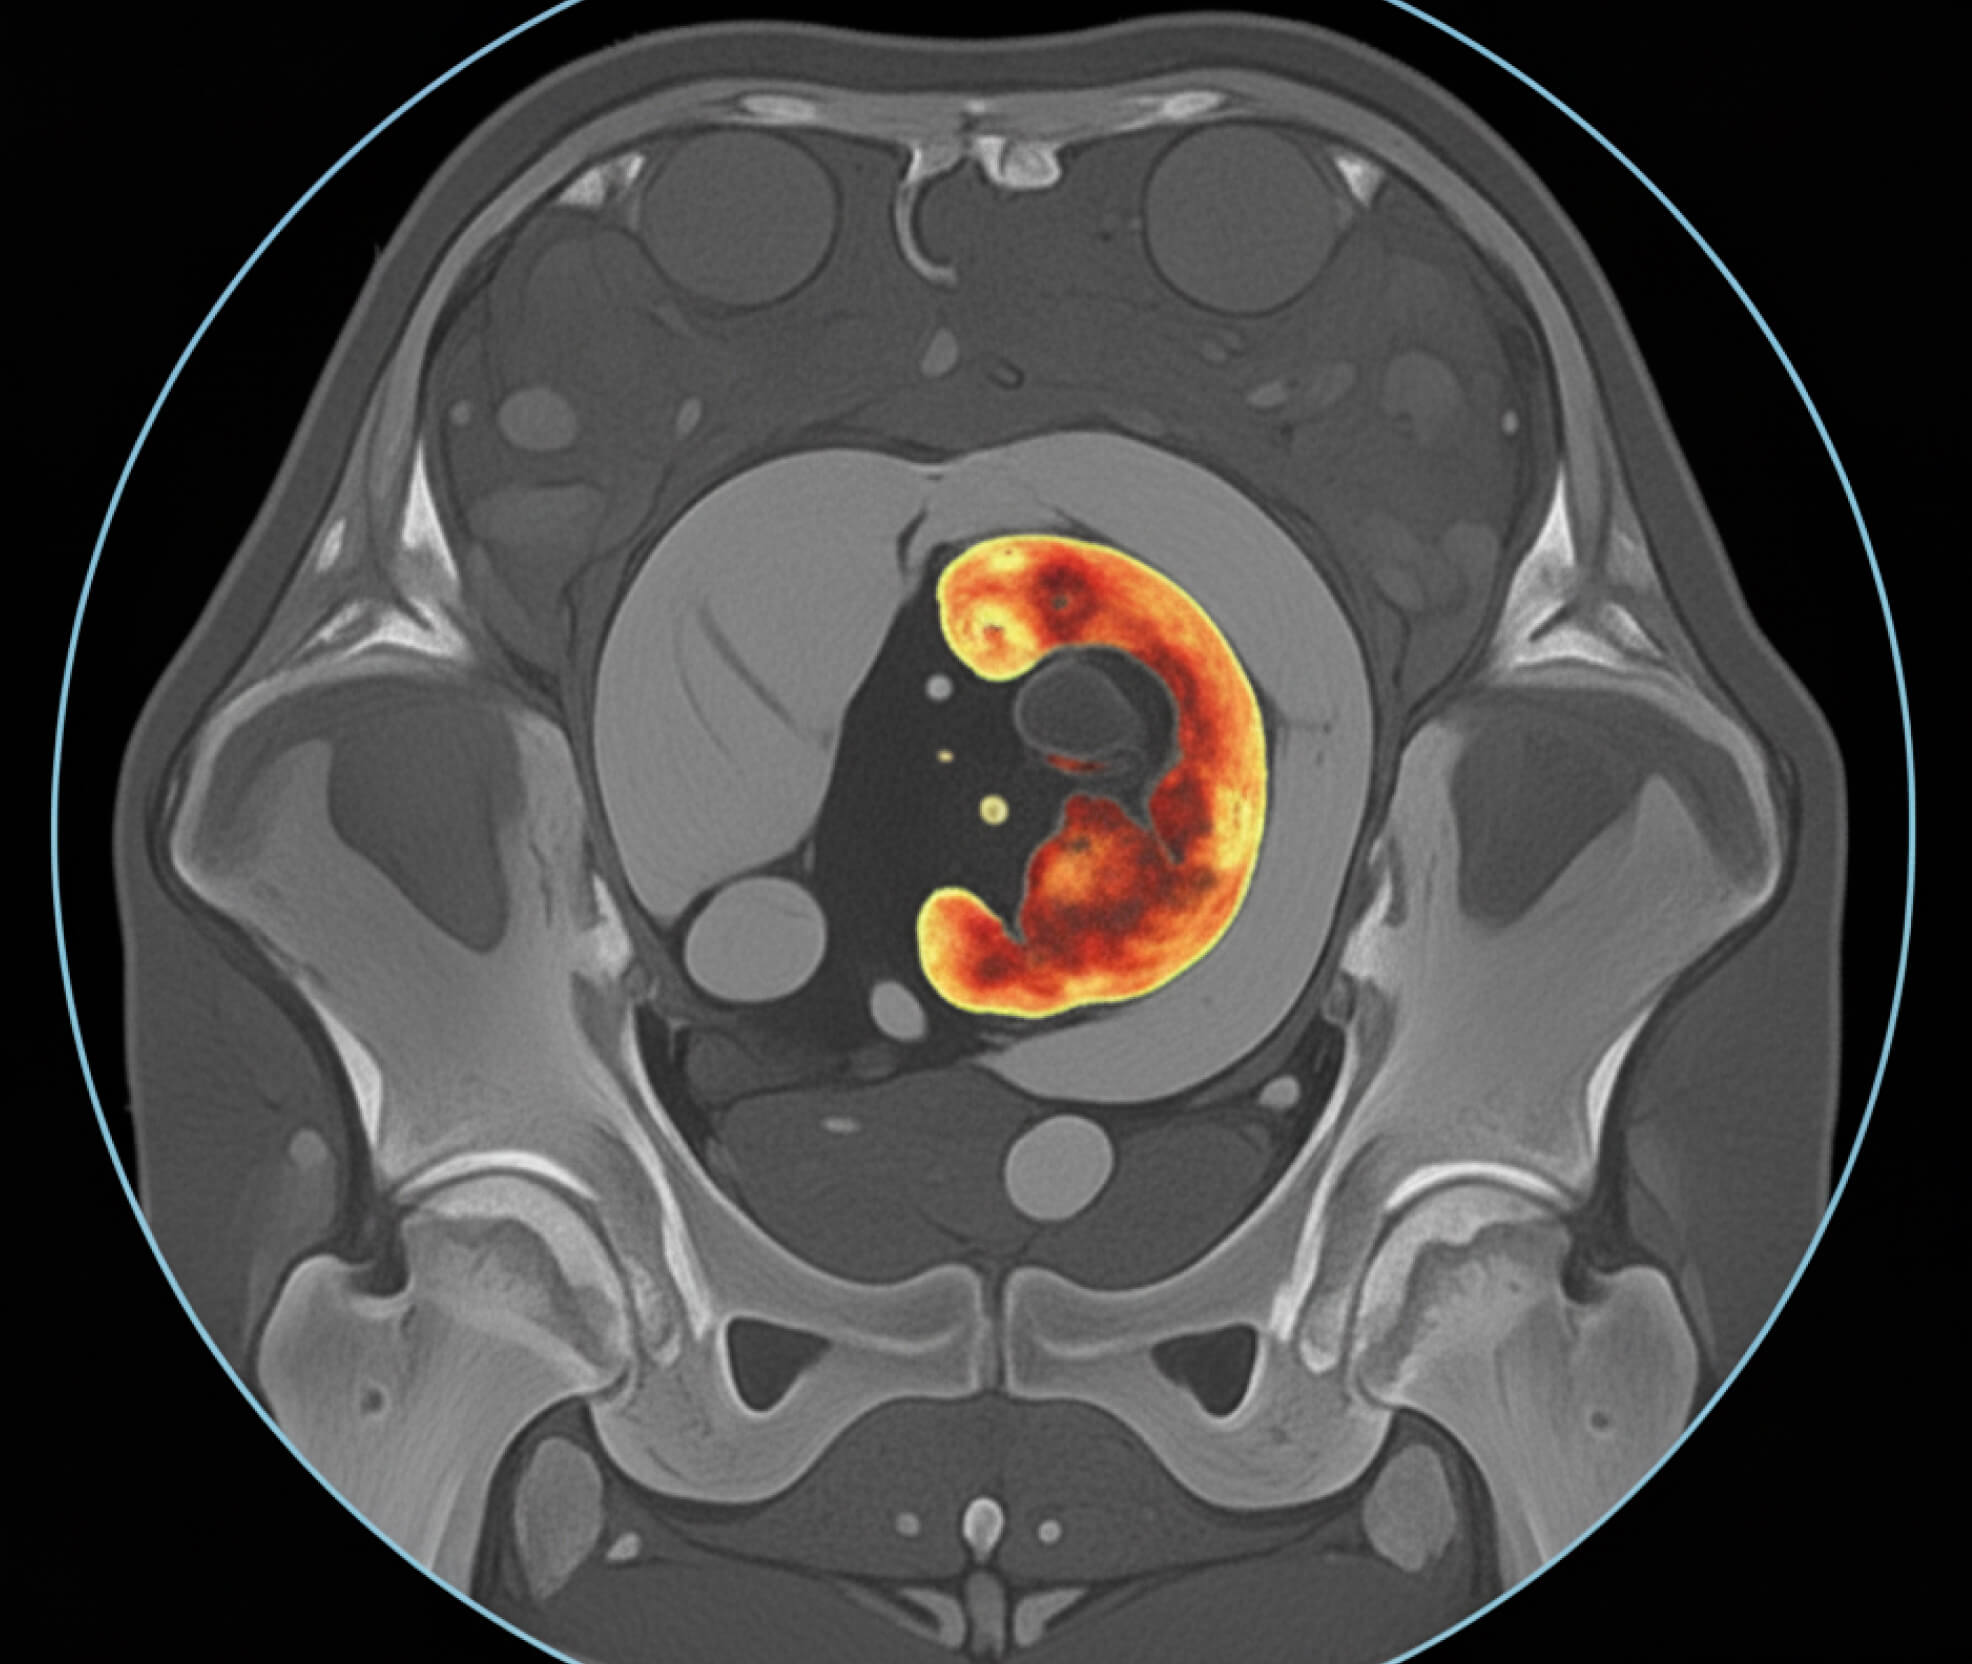

Your doctor may perform a prostate specific antigen (PSA) test. While this test is not considered as a routine screening test, it can be a useful tool to monitor symptoms or if you are at a higher risk of developing prostate cancer. Imaging tests such as an ultrasound or an MRI scan may also be ordered. If needed, referral to a urologist can be provided for further assessment or treatment.